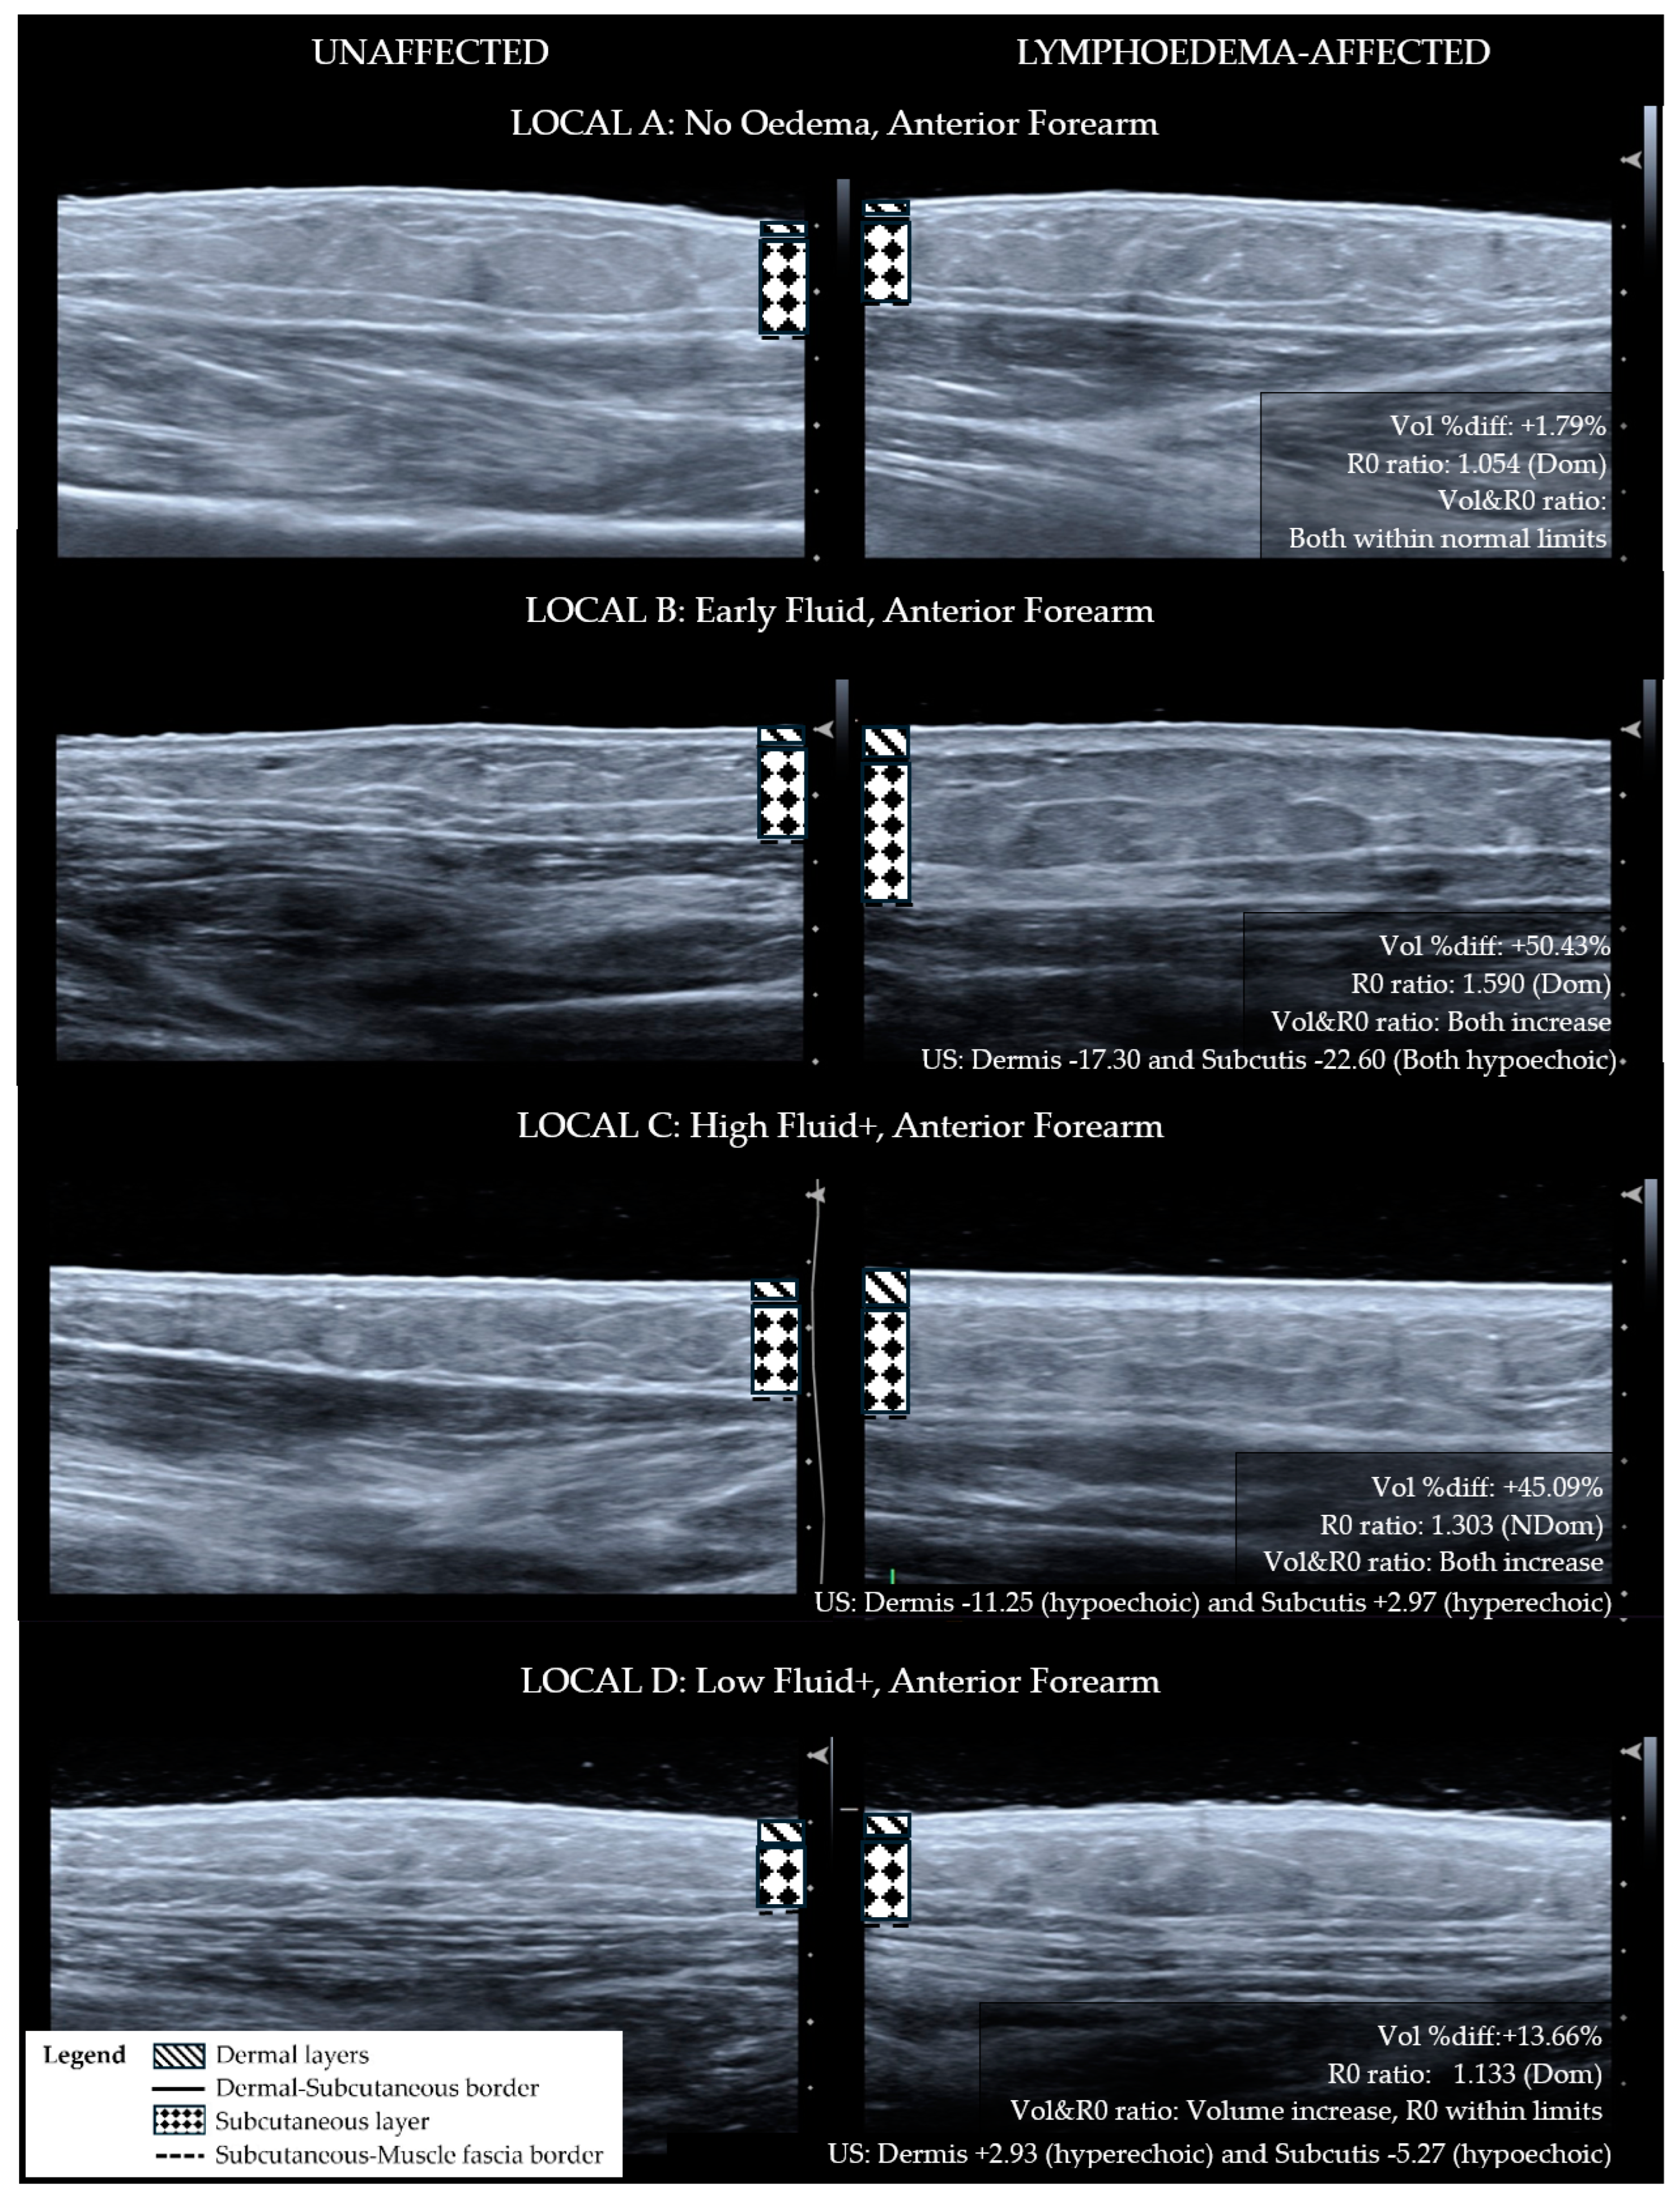

- The ultrasound echogenicity parameter is used to support the presence or absence of tissue compositional change. Lymphoedema tissue has been shown to become hypoechoic (darker) with diffuse fluid influx [15,16] and hyperechoic (lighter) with fibrotic and fatty deposition [17,18,19]. The distribution of hyper-echogenicity may encompass the full or partial cross-section of the tissue layer or appear as scattered flecks [17,18,19]. For this reason, a decrease in the echogenicity of the lymphoedema tissue layers was observed as fluid influx, and an increase in echogenicity escalated the classification to the fibro-fatty groupings.

| A No Oedema | B Early Fluid | C High Fluid+ | D Low Fluid+ |

|---|---|---|---|

| Site does not exhibit lymphoedema characteristics | Tissue exhibits extracellular fluid increase without compositional changes | Tissue exhibits fibro-fatty changes with high fluid volume | Tissue exhibits fibro-fatty changes with low fluid volume |

| Volume- Inter-limb segment difference (% difference between lymphoedema to non-lymphoedema segment) OR Limb segment change (% change from baseline) | |||

| Within normal limits Inter-limb segment: <5.0% (Dom) <3.0% (NDom) OR Limb segment change: <3.0% | May or may not meet inter-limb threshold. OR Exceeds threshold for limb segment change: ≥3.0% | Greater than normal limits Inter-limb segment: ≥5.0% (Dom) ≥3.0% (NDom) OR Limb segment change: ≥3.0% | Greater than normal limits Inter-limb segment: ≥5.0% (Dom) ≥3.0% (NDom) OR Limb segment change: ≥3.0% |

| BIS R0- Inter-limb segment ratio (Unaffected/Affected) | |||

| Within normal limits Forearm: ≤1.1385 (Dom) ≤1.0700 (NDom) Upper Arm: ≤1.1335 (Dom) ≤1.0915 (NDom) | Greater than normal limits Forearm: >1.1385 (Dom) >1.0700 (NDom) Upper Arm: >1.1335 (Dom) >1.0915 (NDom) | Greater than normal limits Forearm: >1.1385 (Dom) >1.0700 (NDom) Upper Arm: >1.1335 (Dom) >1.0915 (NDom) | Within normal limits Forearm: ≤1.1385 (Dom) ≤1.0700 (NDom) Upper Arm: ≤1.1335 (Dom) ≤1.0915 (NDom) |

| Volume and R0 relationship | |||

| Both within normal limits | Both exceed thresholds OR R0 ratio increase and volume decrease, e.g., muscle atrophy or musculoskeletal cause | Both exceed thresholds | Both exceed thresholds. Disproportionate change, i.e., physical volume change large and R0 ratio relatively small OR Opposing direction of change, e.g., volume increase AND R0 ratio less than 1.000 |

| Ultrasound Echogenicity—Lymphoedema API compared to Non-lymphoedema API | |||

| N/A | Dermis: Hypoechoic AND Subcutis: Hypoechoic | Dermis: Hyperechoic OR Subcutis: Hyperechoic | Dermis: Hyperechoic OR Subcutis: Hyperechoic |

| LOCAL Category | Anterior Forearm n (%) | Posterior Forearm n (%) | Upper Arm n (%) |

| A. No Oedema | 1 (6.6) | 1 (6.6) | 4 (26.7) |

| B. Early Fluid | 6 (40.0) | 4 (26.7) | 3 (20.0) |

| C. High Fluid+ | 4 (26.7) | 6 (40.0) | 4 (26.7) |

| D. Low Fluid+ | 4 (26.7) | 4 (26.7) | 4 (26.7) |

| Total (n) | 15 (100) | 15 (100) | 15 (100) |